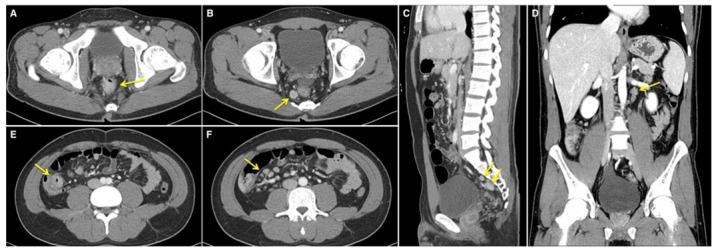

The incidence of rectal neuroendocrine tumor (NET), which is often diagnosed during routine surveillance endoscopy, is increasing. The majority of these tumors are small and asymptomatic, possessing benign features with favorable prognoses. At present, small rectal NETs without high-risk factors are typically treated by local resection, including endoscopic mucosal resection, endoscopic submucosal dissection, or transanal endoscopic microsurgery, with or without additional imaging follow-up by abdominal computed tomography or magnetic resonance imaging. The present study, however, describes a case of a small rectal NET without any known risk factors, which was accompanied by substantial locoregional lymph node metastasis, underscoring the importance of imaging studies for rectal NETs.

直肠神经内分泌肿瘤(NET)的发病率正在上升,这类肿瘤常在常规监测性内镜检查时被诊断出来。这些肿瘤大多体积小且无症状,具有良性特征,预后良好。目前,无高危因素的小直肠NET通常采用局部切除治疗,包括内镜黏膜切除术、内镜黏膜下剥离术或经肛门内镜显微手术,术后可进行或不进行腹部计算机断层扫描或磁共振成像的额外影像学随访。然而,本研究描述了一例无任何已知危险因素的小直肠NET病例,该病例伴有大量局部区域淋巴结转移,强调了直肠NET影像学检查的重要性。